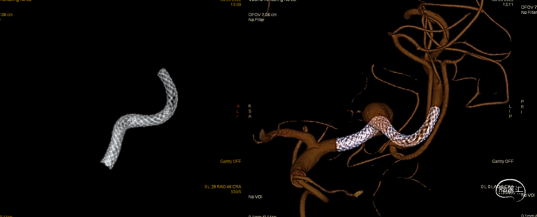

Pipeline™ Flex 4.0*20mm血流导向装置

术中Dyna-CT可见支架打开充分且贴壁良好。

支架远端释放10mm,确认支架打开后整体回撤至计划铆钉点 利用推拉技术让支架在载瘤动脉内充分打开

最后支架尾端减张释放,减影像及Dyna-CT可见支架完全打开且贴壁良好